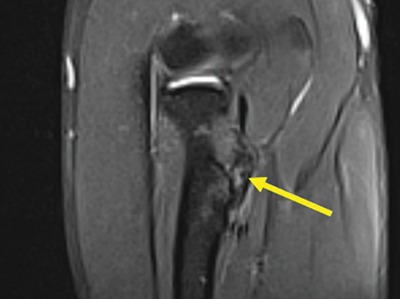

Three patients (1.5%) had an altered signal intensity in the biceps tendon. One patient had a score of 1 (Figure 5), and the other two had a score of 2 (Figure 6).

Coronal fat-saturated T2-weighted image at the level of the biceps tendon insertion with an irregular T2-hyperintense signal within, score 2.